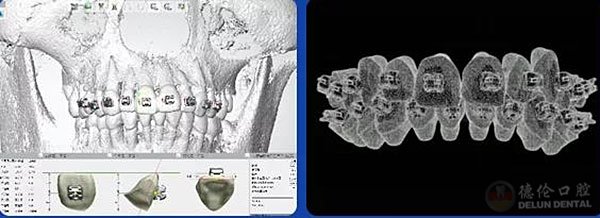

“智能正畸导航系统”生成的“智能正畸粘接导板”,即数字化间接粘接技术,是通过数字化口扫采集口内牙齿数据,及数字化准确设计,再以数字化3D打印技术打印成数字化粘接托槽导板。

结合三维CBCT数据,医生视野更全面,更准确预测牙齿牙根移动,制定可靠的矫治方案。